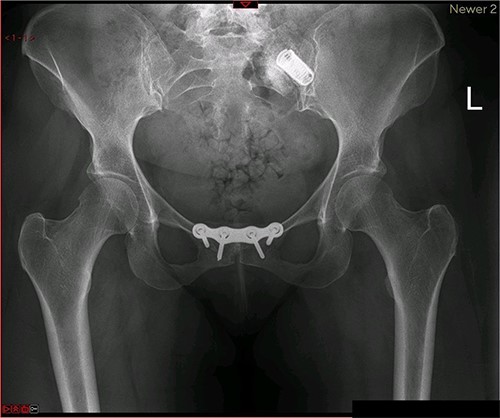

Postoperative X-ray of the pelvis following the first fusion surgery: postoperative X-ray of the pelvis, performed in November 2014 following the first fusion surgery, showing plating of the symphysis pubis and distraction arthrodesis of the left sacroiliac joint with DIANA implant.